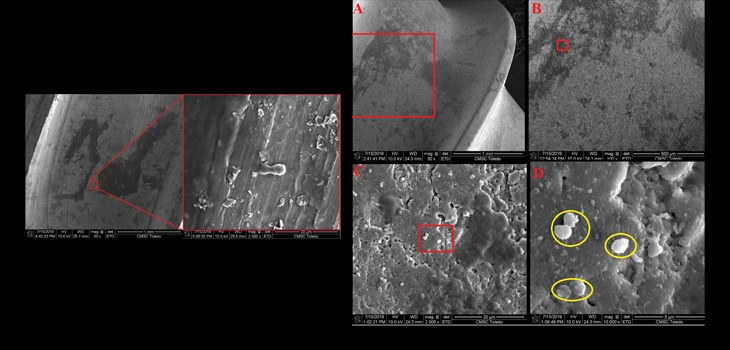

Posted inSpine Are Your Sterile Implants Really Sterile? by Kimberly DelMonico October 18, 2018October 24, 2024